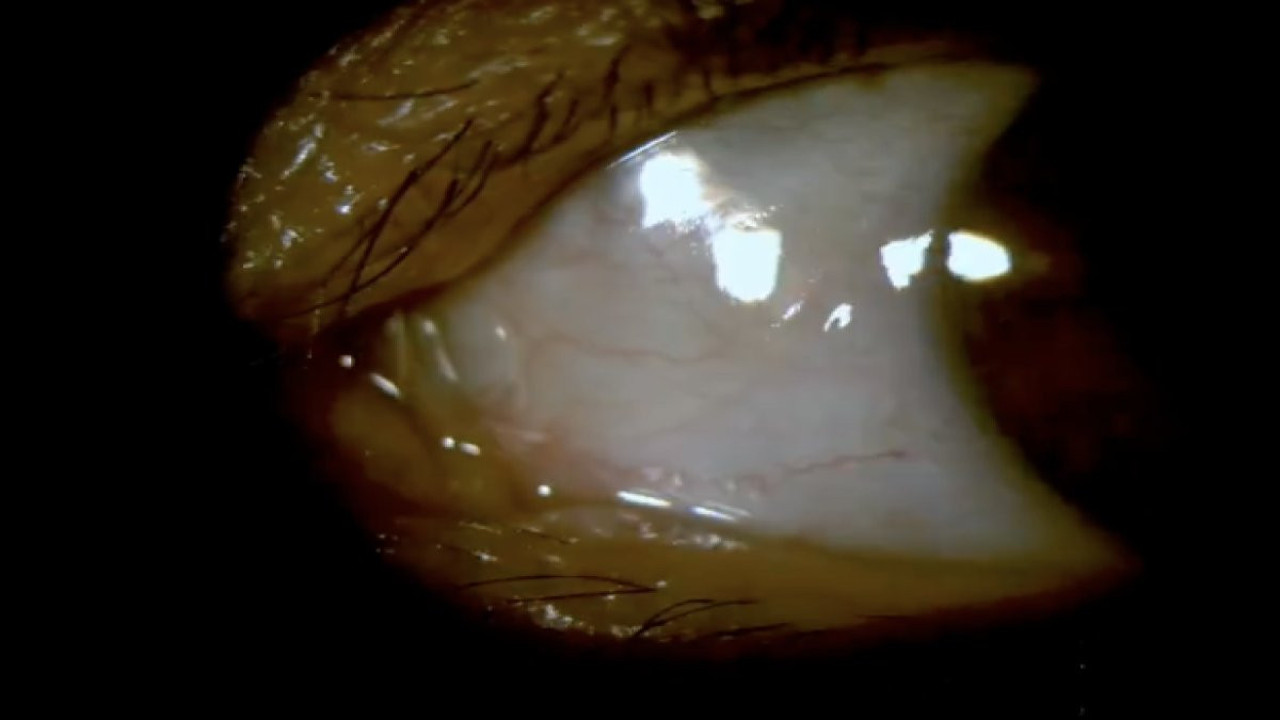

Bir hasta, lensini düşürdüğünü düşünerek batma şikayetiyle göz doktoruna başvurduğunda, doktorlar tarafından yapılan muayene sırasında şaşırtıcı bir gerçek ortaya çıktı. Hasta, aslında lensinin gözün arkasına kaçtığını öğrendi.

Hastanın batma şikayeti üzerine yapılan muayenede, lensin göz yüzeyinde olmadığı ve normal bir şekilde düşmediği tespit edildi. Daha detaylı bir inceleme sonucunda, lensin gözün arkasına, yani göz içine kaçtığı belirlendi.

Bu durum, göz doktorları için oldukça nadir görülen bir durum olarak kabul ediliyor. Lensin gözün arkasına kaçması, hem hastanın sağlığı açısından hem de lensin kullanımı açısından ciddi bir sorun teşkil edebilir.